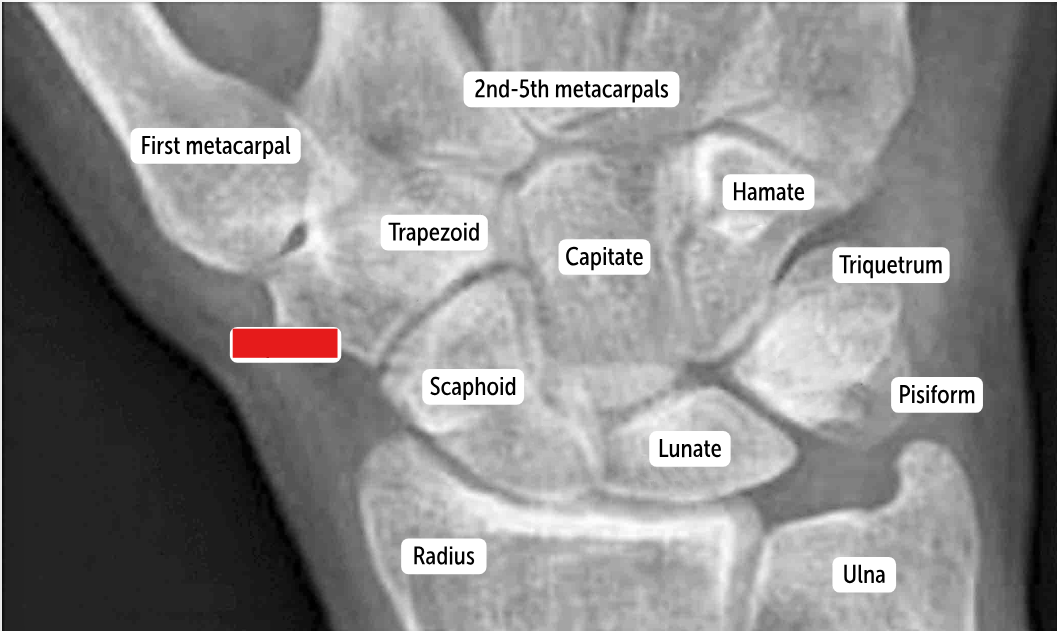

The most commonly fractured carpal bone by falling on an outstretched hand, which has a risk of avascular necrosis, is the __________.

Scaphoid bone

The most commonly dislocated bone after a fall on an outstretched hand is the ___________.

Lunate bone

Carpal bones by row:

So Long To Pinky, Here Comes The Thumb

Scaphoid, Lunate, Triquetrum, Pisiform, Hamate, Capitate, Trapezoid, Trapezium

Scaphoid

Lunate

Triquetrum

Pisiform

Hamate

Capitate

Trapezoid

Trapezium

The two distinct rows articulate with each other at the __________. It’s a plane (simple sliding) joint that acts to amplify all the other wrist actions.

midcarpal joint

Which carpal bones articulate with the metacarpal bones?

The bones of the distal row (hamate, capitate, trapezoid, and trapezium) articulate with the metacarpal bones.

The carpals form the floor of a “tunnel” covered by a ligament called the ______________. This carpal tunnel allows tendons, nerves, and blood vessels to cross the wrist and enter the hand.

flexor retinaculum